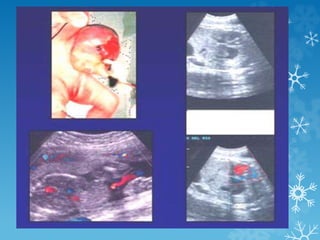

 La exposición fetal a

inhibidores de la ECA como

agentes antihipertensivos

produce oligohidramnios,

muerte fetal, hipoplasia de

los huesos de la bóveda

craneal, RCIU y disfunción

renal.